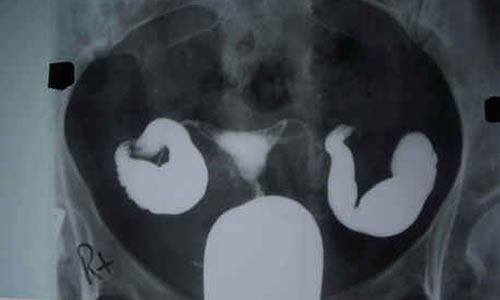

rahim filmi.jpg

Selâmün alykm.Ben 2yıllık evliyim arkadaşlar.yaşım da 28e geliyor o yüzden o kadar çok istyrm ki.içimi dökmek istedim burda.evlendikten 2ay sonra hamile kalmştm.bebeğimn 26.haftada kalbini durduğunu öğrenmiştim.sebebi bulunamadı.Nasip değilmş dedm..3ay korunup tekrar gebe kaldım ama o da boş gebelikti.geçen sene kasımda kürtaj oldm sonra çok aşırı kanama oldu.1yıldır hamile kalamıyorum.doktor hsg deyince bu ay 8inde çektrdm çok kolay geçti elhamdülillah.Yumurtalık kanalları tıkalı dedi ama ilaçla açılmş şükür ki.şu an adetm 2gün geçti.yoğun Sarı beyaz arası akıntı geliyor.her lavaboya gidişimde kalbim nasıl çarpıyor.test yapmadım eşim yasakladı her ay alıp sonucunda çok ağladığm için.Rabbim tüm isteyenlere nasip etsin istedikleri anda.kimseyle paylaşamyrm bunları.herkes sitres yaparsan olmaz lafını söylüyo daha çok gerilyrm.rüyamda bana teheccüde kalKyo musun hamile kalmak için diyorlar.bu ay çok şükür kalktım çok dua ettm Rabbim kabul etsn.bir de Peygamber Efendimiz SAV in Hadis i Şerifte Cuma gecesi Yasin ve arkasından Sad Suresini okuyanın duasının geri çevrilmeyecği müjdesini duydum yaptm. Çok uzun oldu hakkınızı helal edin..Allah dualarmzı kabul etsn vakti gelmiştir İnşaAllah